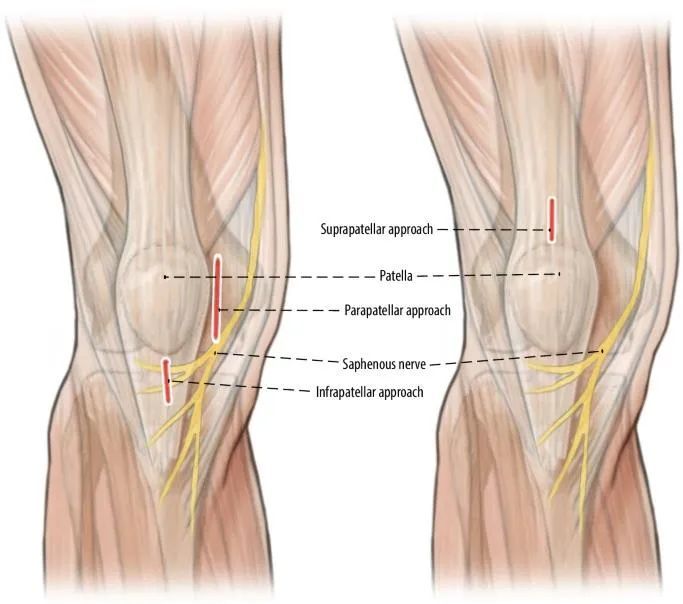

Nyeri dengkul anterior postoperative mangrupikeun masalah anu relevan. nyeri dengkul anterior geus dilaporkeun dina 50-70% pasien kalayan fractures, kalawan ngan 30% pasien ngalaman relief nyeri sanggeus ngaleupaskeun endplate nu. Pembentukan tapak tatu anu aya hubunganana sareng urat patellar sareng pad lemak Hoffa diperkirakeun janten sumber poténsial nyeri dengkul pasca operasi. Sajaba ti éta, pendekatan suprapatellar avoids incision tradisional severing cabang cabang patellar saraf saphenous, nu avoids numbness dengkul anterior sarta sensasi dulled (Gambar 4). Ngaliwatan paku ngaliwatan urat quadriceps, kukituna ninggalkeun urat patellar gembleng, sigana nyata ngurangan laju nyeri dengkul postoperative.

Gbr. 4 Hubungan antara saraf saphenous sareng aksés anu béda kana paku tibialis obliqua